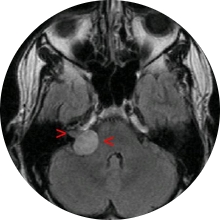

Mujer de 31 años, con crisis fármaco-resistentes desde los 2 años de edad. Sin antecedentes de interés.

La paciente es intervenida quirúrgicamente bajo control neurofisiológico para preservar la...

El abordaje se realiza a través de una craneotomía pterioral y se utilizan técnicas microquirúrgicas aspirador...